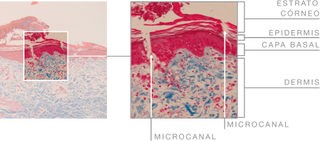

Microneedling is a minimally invasive technique that creates thousands of epidermal microcanals that allow substances to pass through the horny layer of the skin, while simultaneously producing dermoepidermal biostimulation, incrementing the activity of the drug substances.

DEMONSTRATED EFFICACY

In vivo histological view showing the microcanals formed with the microneedling technique.